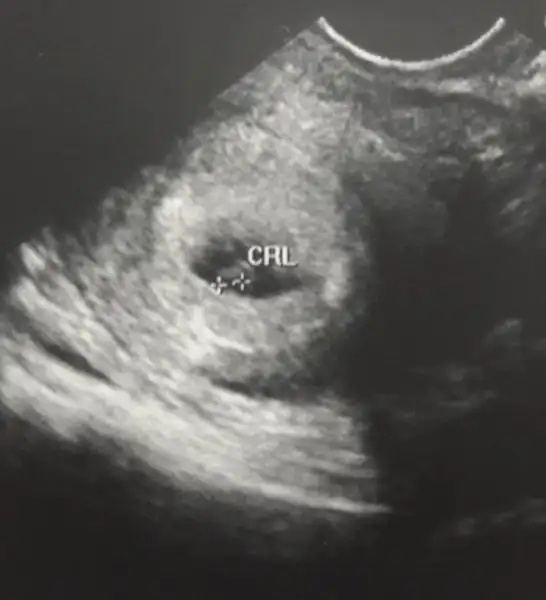

Yine kendi kendime evhamlanıyor muyum yoksa bir sıkıntı mı var anlayamadım .. Ayın 9 unda 79 du bugün 1913 .. Bilgisi olan var mı ?